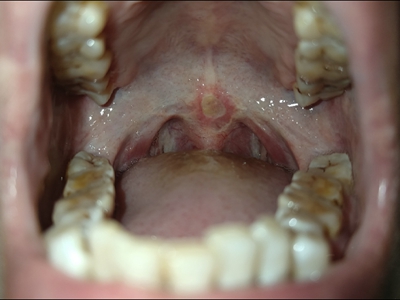

口腔溃疡又称复发性口疮,是慢性的口腔黏膜小溃疡,深浅不等,为圆形或椭圆形损害,可反复和周期性复发。多发生于口腔非角化区,如唇黏膜、舌头等处,预后较好,可自行痊愈。

口腔溃疡为圆形或椭圆形,直径0.2-0.5cm,溃疡单个或由数个连成一片,溃疡表浅边缘整齐,外观呈灰黄色或灰白色,上覆盖黄白渗出膜,周围黏膜充血、水肿而有红晕。

皮损局部有烧灼样疼痛,于进餐时加重,影响进食、说话。严重溃疡直径可达1-3cm,深及黏膜下层甚至肌肉。